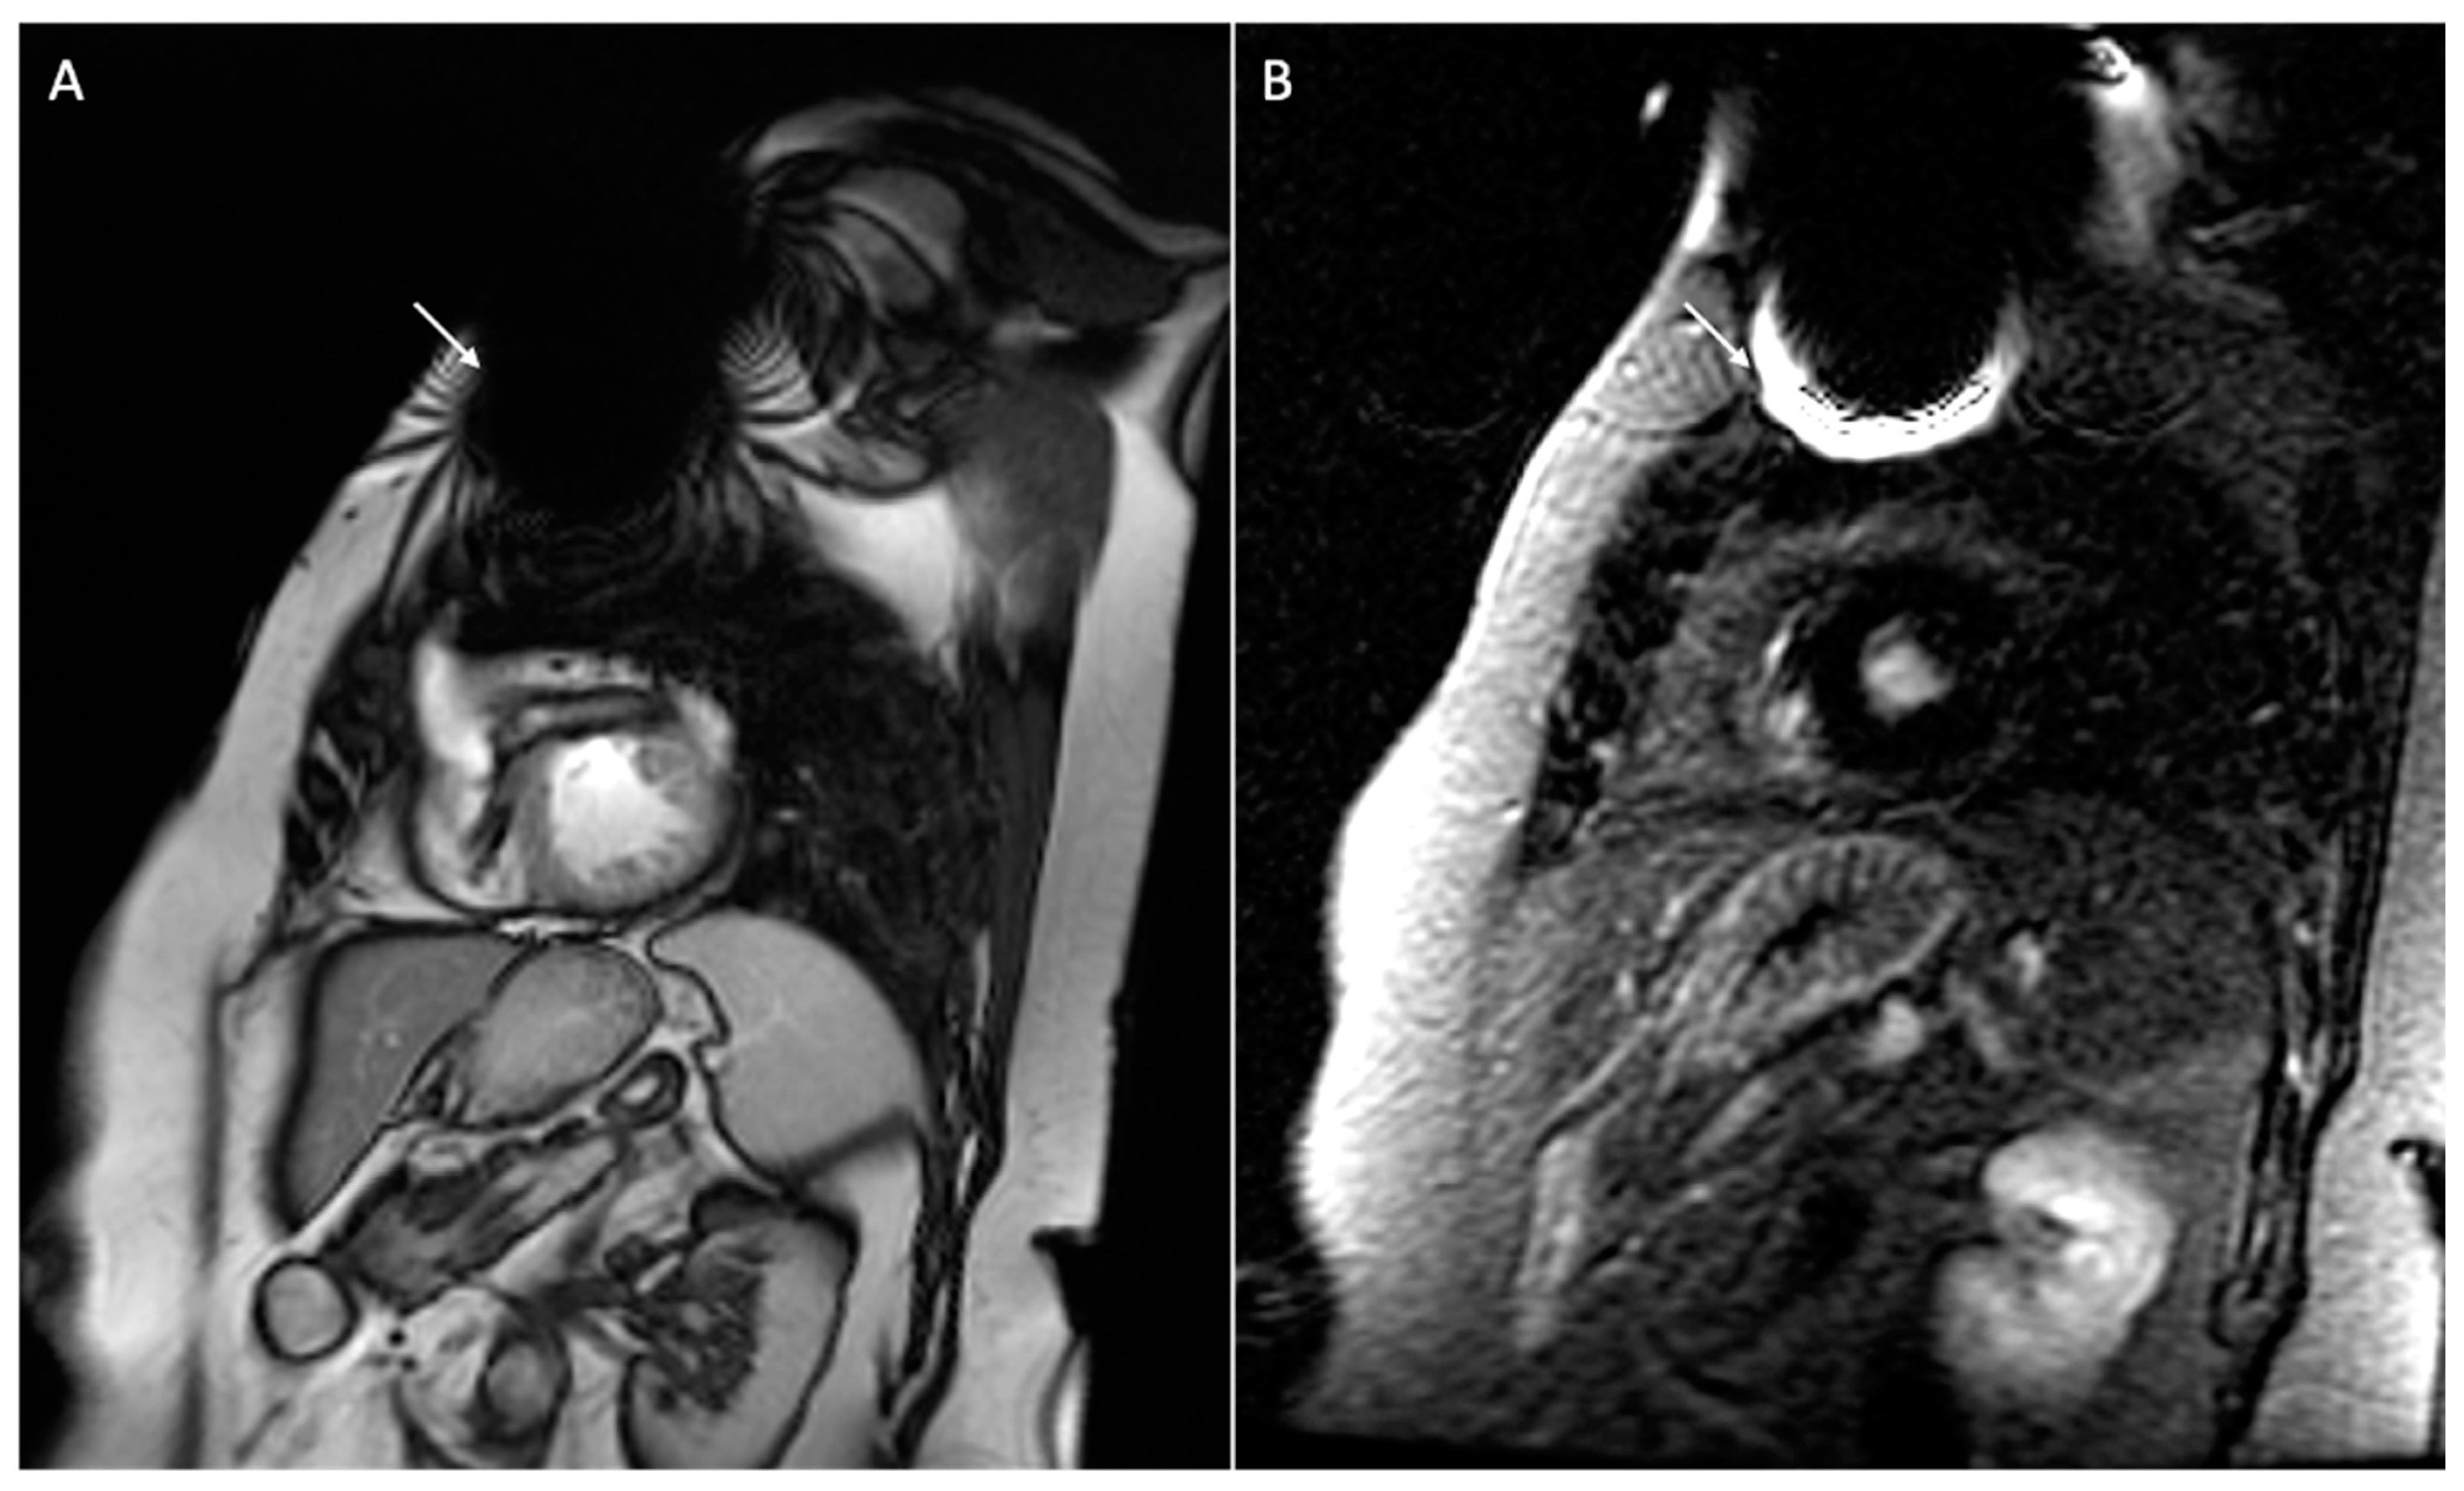

6. Issue: Artifact